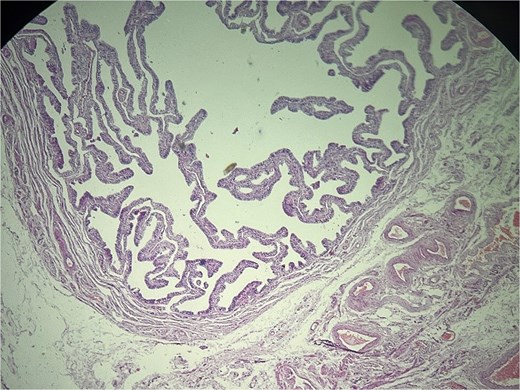

Microscopic evaluation (hematoxylin and eosin) demonstrated an endometrial polyp without atypia, multiple leiomyomas, and bilateral benign serous cystadenomas. Sections from the left fallopian tube and adjacent mesosalpinx revealed a small, well-circumscribed nodule (~3 mm) within the mesosalpinx (Figs 1–3). The nodule was composed of bland polygonal cells with distinct borders and clear to finely granular eosinophilic cytoplasm. Nuclei were round to oval, centrally located, and uniform, without pleomorphism, hyperchromasia, necrosis, or increased mitotic activity. The cells were arranged in nested/trabecular architecture resembling zona fasciculata; no medullary component was identified. These features supported the diagnosis of ectopic adrenal cortical tissue.

Left fallopian tube and adjacent mesosalpinx without significant histopathologic abnormality. Hematoxylin and eosin (H&E) stain, ×40.